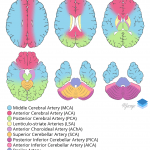

- Watershed territory infarct

Areas of low attenuation in the left frontoparietal white matter in a distribution most suggestive of ACA/MCA watershed territory ischemia. No significant associated mass effect or evidence of hemorrhagic transformation.